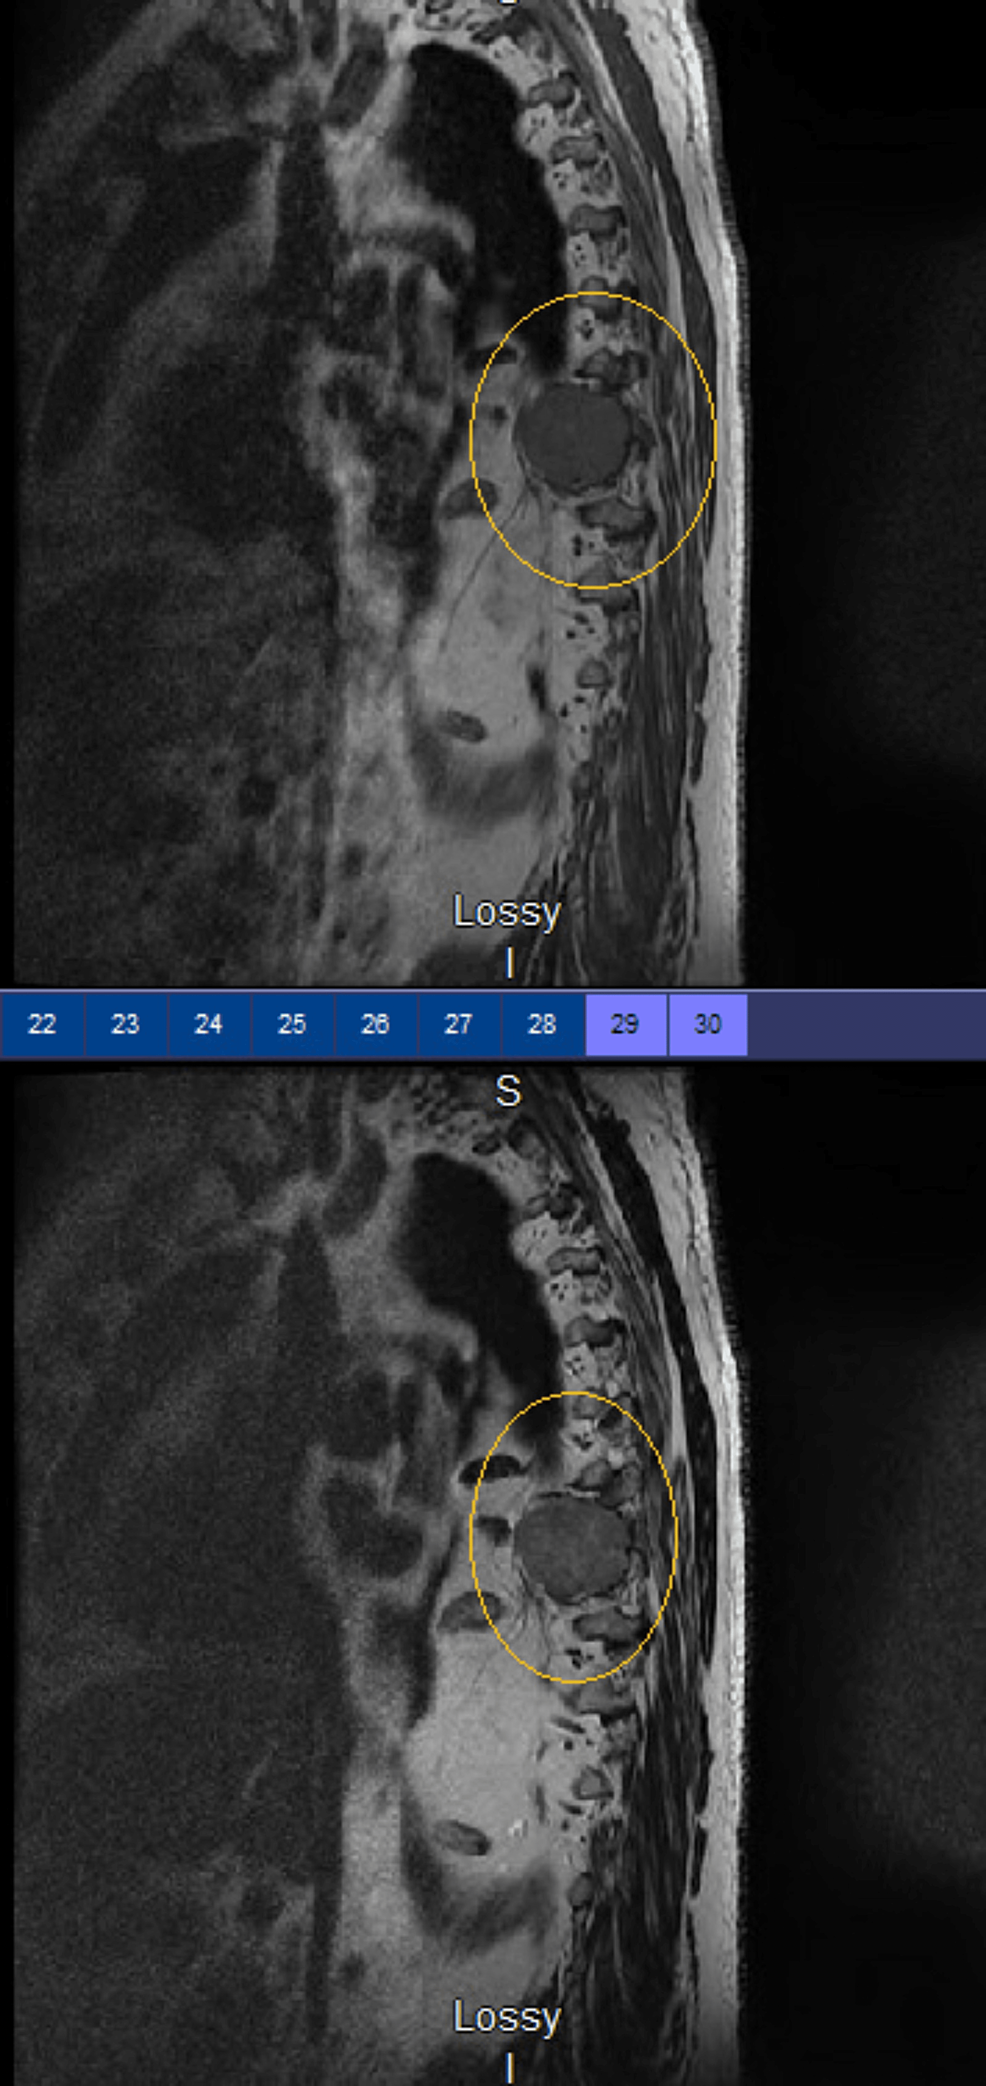

Axial and sagittal slices of MRI thoracic spine without contrast What Is Mri Thoracic Spine Without Contrast mri joint without and with contrast upper extremity lower extremity. about mris without contrast. It creates clear, detailed pictures of the. for patients with known allergies to contrast material or those with compromised kidney function, mri without contrast becomes a safer. a thoracic spine mri provides detailed images of the vertebrae, soft tissues, and surrounding organs. What Is Mri Thoracic Spine Without Contrast.